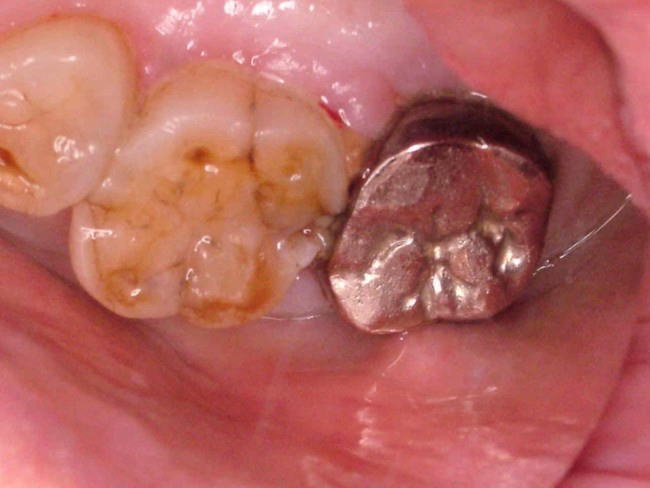

このうち健診などで見落としがちになるのが隣接面う蝕です。隣接面う蝕を初期のうちに見つけるには私たち歯科医でもかなり経験と熟練を要します。歯間離開器という器具を用いて隣り合う歯を少し開いてみないとなかなか分りません。下の写真は数ヶ月前には見つけられなかった隣接面う蝕のレントゲン像と口腔内写真です

写真で左の歯(上顎第一大臼歯)が右の金属冠に接するところで隣接面う蝕になっています。